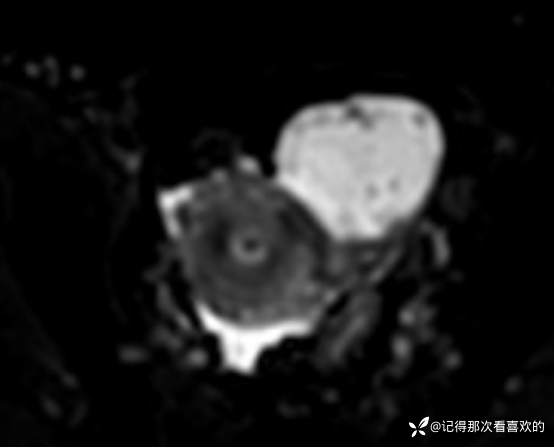

入院后查十二通道常规心电图:1、窦性心律2、逆钟向转位。余相关检验未见明显异常。于2025.05.30在静脉麻醉下行“宫腔镜诊断性刮宫术”,术顺,术后病理(2508387):(宫内容物)子宫内膜息肉。查心脏彩超(Z250530002):三尖瓣轻度反流。双侧下肢深静脉血管彩色多普勒超声(Z250530003):双侧下肢股总静脉反流,考虑双侧下肢深静脉瓣功能不全。经阴道彩超检查(Z250530004):双侧附件区低回声不均团块,考虑MT,建议进一步检查。子宫多发肌瘤。子宫内膜区低回声结节,考虑粘膜下肌瘤可能。宫颈腺体多发囊肿。盆腔MRI增强(MR109286):1.双侧附件区团块状占位,考虑MT,请结合临床。2.子宫肌层内、浆膜下多发肌瘤。3.子宫腔内异常结节灶,粘膜下肌瘤可能。4.盆腔少量积液。5.右侧髂骨内结节灶,性质待定,建议进一步检查。胸部CT(CT384707):1.双肺多发微小结节,建议随诊复查。2.气管憩室。3.扫及右肾结石?新上腹部CT平扫(CT384838):盆腔右侧占位性病变,请结合临床及MRI检查。HPV+TCT:HPV阴性;非典型鳞状上皮细胞(不能明确意义)。2025.06.03行胃肠镜,电子胃十二指肠镜检查(PG25003031):胃体溃疡(待病理);慢性萎缩性胃炎。电子结肠镜检查(PC25002608):结肠多发息肉(内镜下息肉切除+钳除)。快速石蜡病理(2508504):胃体:低分化腺癌,伴少量印戒细胞癌成分,免疫组化结果待补充报告。快速石蜡病理(2508505):降结肠:增生性息肉。